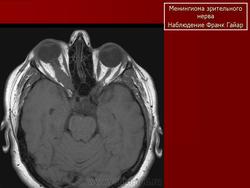

Менингиома зрительного нерва.

Менингиома зрительного нерва (син.: менингиома оболочки зрительного нерва)

Доброкачественная, медленно растущая опухоль оболочки интраорбитальной части зрительного нерва. 90% менингиом глазницы представляют собой вторичные образования, произрастающие из тканей, прилежащих к глазнице. В первую очередь требуется проведение дифференциальной диагностики с глиомой зрительного нерва (не содержит кальцинатов).

Наиболее типичная черта: объемное образование, расположенное вдоль интраорбитальной части зрительного нерва, накапливающее КВ и содержащее обызвествления по типу трамвайных рельс. Форма: тубулярная (65%) > на ножке (25%) > веретеновидная (10%). Формируется вокруг нерва, реже растет эксцентрично или имеет ножку

На КТ срезах без контрастного усиления менингиома зрительного нерва выглядит изоденсной. Типично наличие линейных или точечных обызвествлений. Симптом «трамвайных рельс» отражает накопление КВ по сторонам гиподенсного зрительного нерва или наличие обызвествлений в структуре опухоли. Как правило, наиболее дистальная часть зрительного нерва, в месте его вхождения в глазное яблоко, не содержит обызвествлений.

При исследовании необходимо определить расположение бляшковидной менингиомы относительно бугорка турецкого седла и пластинки клиновидной кости, так как данный тип опухоли может распространяться интракраниально через канал зрительного нерва. КТ не позволяет адекватно визуализировать интракраниальное распространение опухоли, которое может привести к развитию двусторонней слепоты.

Менингиома зрительного нерва

Менингиома оболочки зрительного нерва.